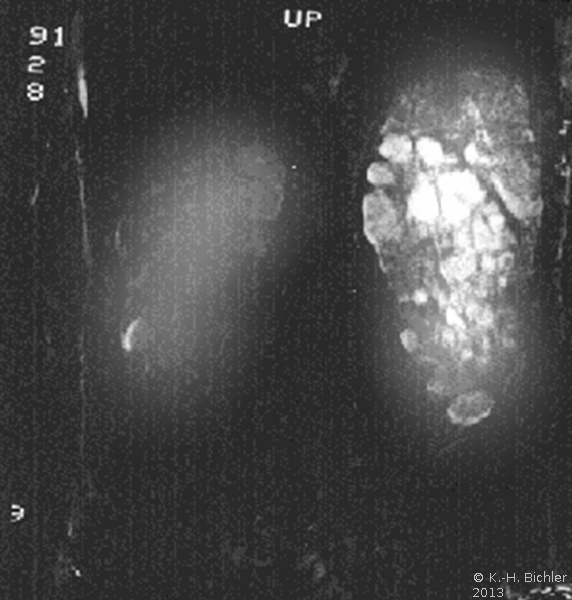

Die Diagnose wird mittels Anamnese (zystische Nierenerkrankungen in der Familie), RR-Messung, Labor (Kreatinin) mit genetischer Untersuchung, Sonographie, Computertomographie und gegebenfalls Kernspintomographie gestellt (Abbildung 4).

Ein i.v.-Pyelogramm kann im Rahmen der differentialdiagnostischen Abklärung des Flankenschmerzes indiziert sein (Abbildung). Sofern schon eine ausgeprägte Niereninsuffizienz vorliegt, sollte die Abklärung mit einem retrograden Pyelogramm erfolgen (Abbildung 5).